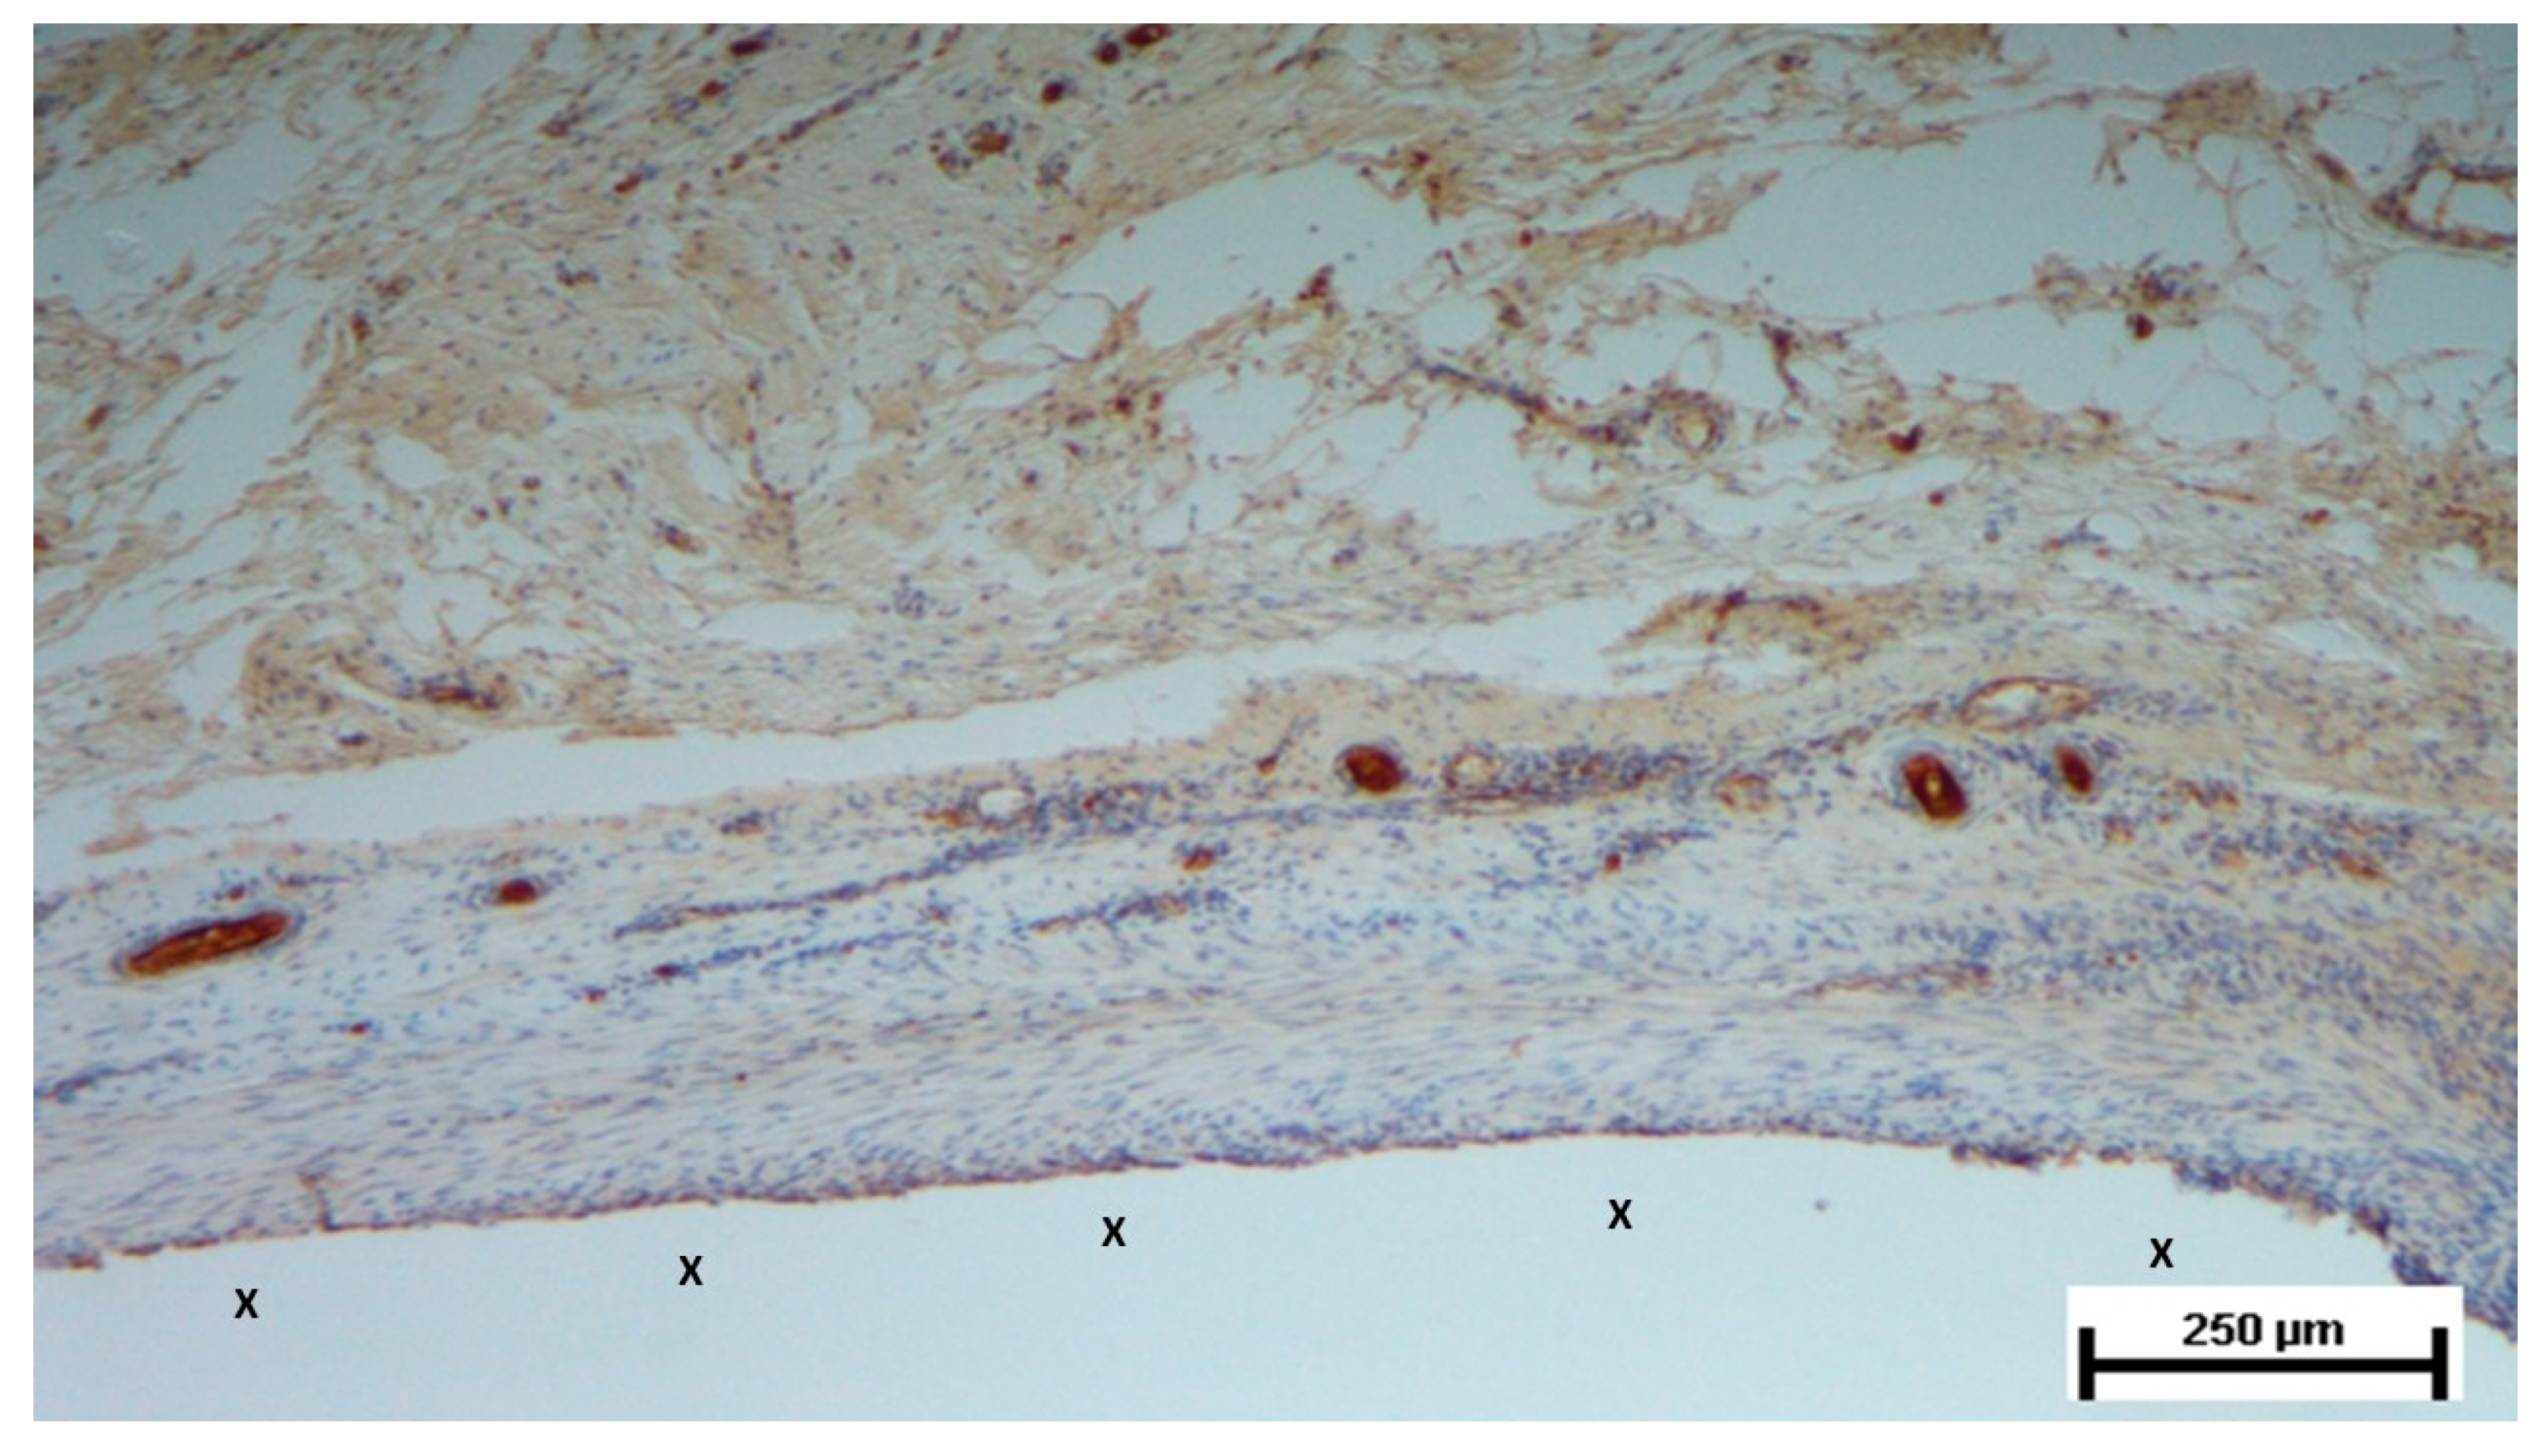

Figure 10. Biopsy taken four months post-implantation from the 3D scaffold of the S&S Hernia System. Numerous vascular elements in advanced stage of development (stained in brown), close to the S&S fabric (X). CD31 50X.

In the mid-term period (3-4 months post-implantation), H&E staining showed a significant presence of vascular structures within the S&S device. Notably, in this postoperative period no signs of inflammatory response against the fabric of the S&S device could be evidenced. The arterial structures displayed advanced development, with well-defined endothelial and muscular layers, while the adventitia was properly enveloping the vessels. Similarly, the veins exhibited noticeable structural maturation compared to the earlier period (Figure 7, Figure 8 & Figure 9).